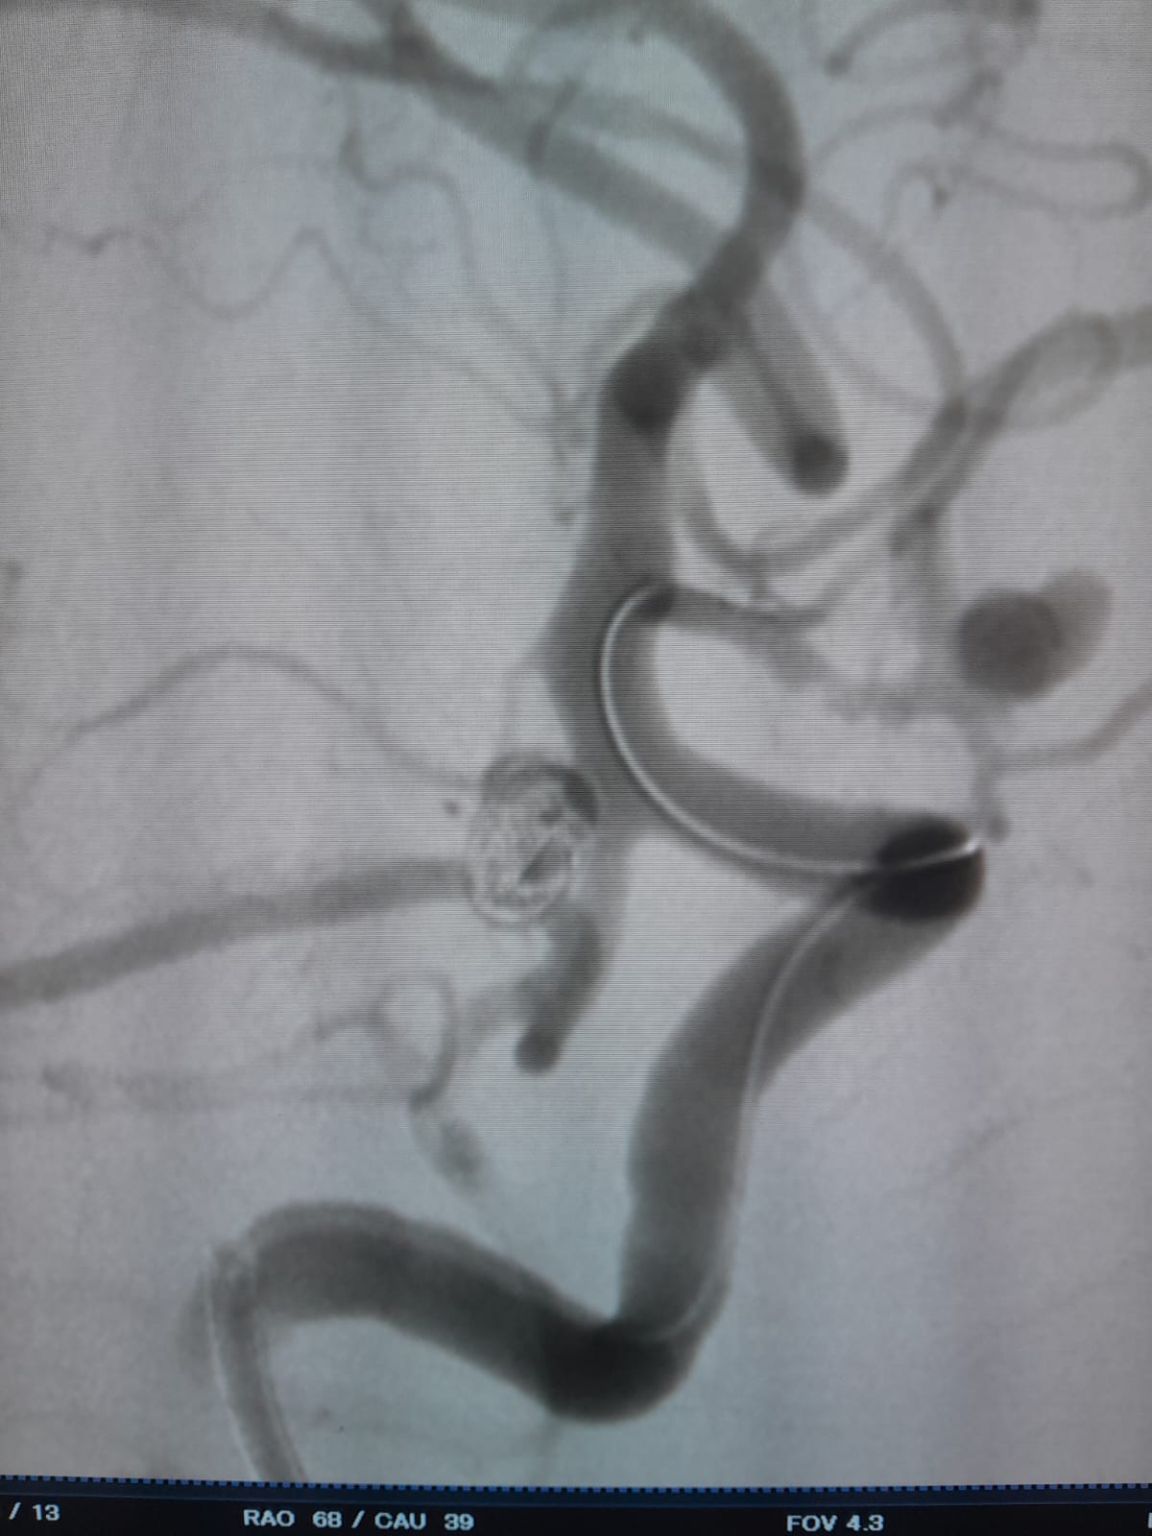

Во время наблюдения было отмечено остаточное наполнение в ранее обработанной аневризме задней сообщающейся артерии. Команда повторно зашел на сайт с помощью Frepass®Одноразовый микрокатетер (TJMC18 Plus) и успешно развернутый Nuva®Отвод потока (TJED-D-4.5-16), который продемонстрировал идеальное расположение стены и отличное отклонение потока, что привело к весьма удовлетворительным результатам лечения.